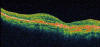

Paciente previamente diagnosticada de DMAE atrófica en ambos ojos que acude a nuestra consulta para valoración presentando una agudeza visual de 0,05 en el ojo derecho y de 0,86 en ojos izquierdo. En el fondo de ojo se observa maculopatía atrófica en ambos ojos con restos de sangre en el ojo derecho perifoveal. En la imagen OCT se observa la clara diferencia en definición de imagen con respecto al fluido subretiniano del Stratus (fig. 7) en comparación con el Cirrus (fig. 8) y la escala de colores utilizada por éste (fig. 9).

Fig. 7: Fluido subretiniano subfoveal por membrana neovascular visto por el

Stratus.

Fig. 8: Fluido subretiniano subfoveal por membrana neovascular visto por el

Cirrus.